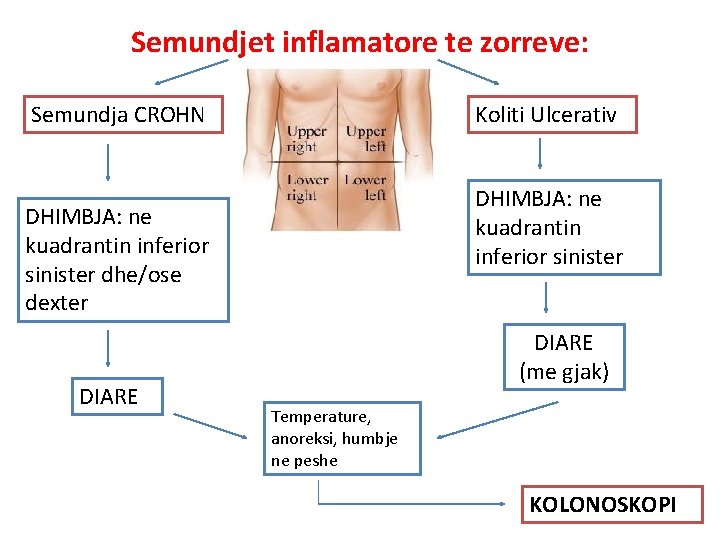

Semundjet inflamatore te zorreve: Semundja CROHN Koliti Ulcerativ DHIMBJA: ne kuadrantin inferior sinister dhe/ose dexter DIARE (me gjak) Temperature, anoreksi, humbje ne peshe KOLONOSKOPI